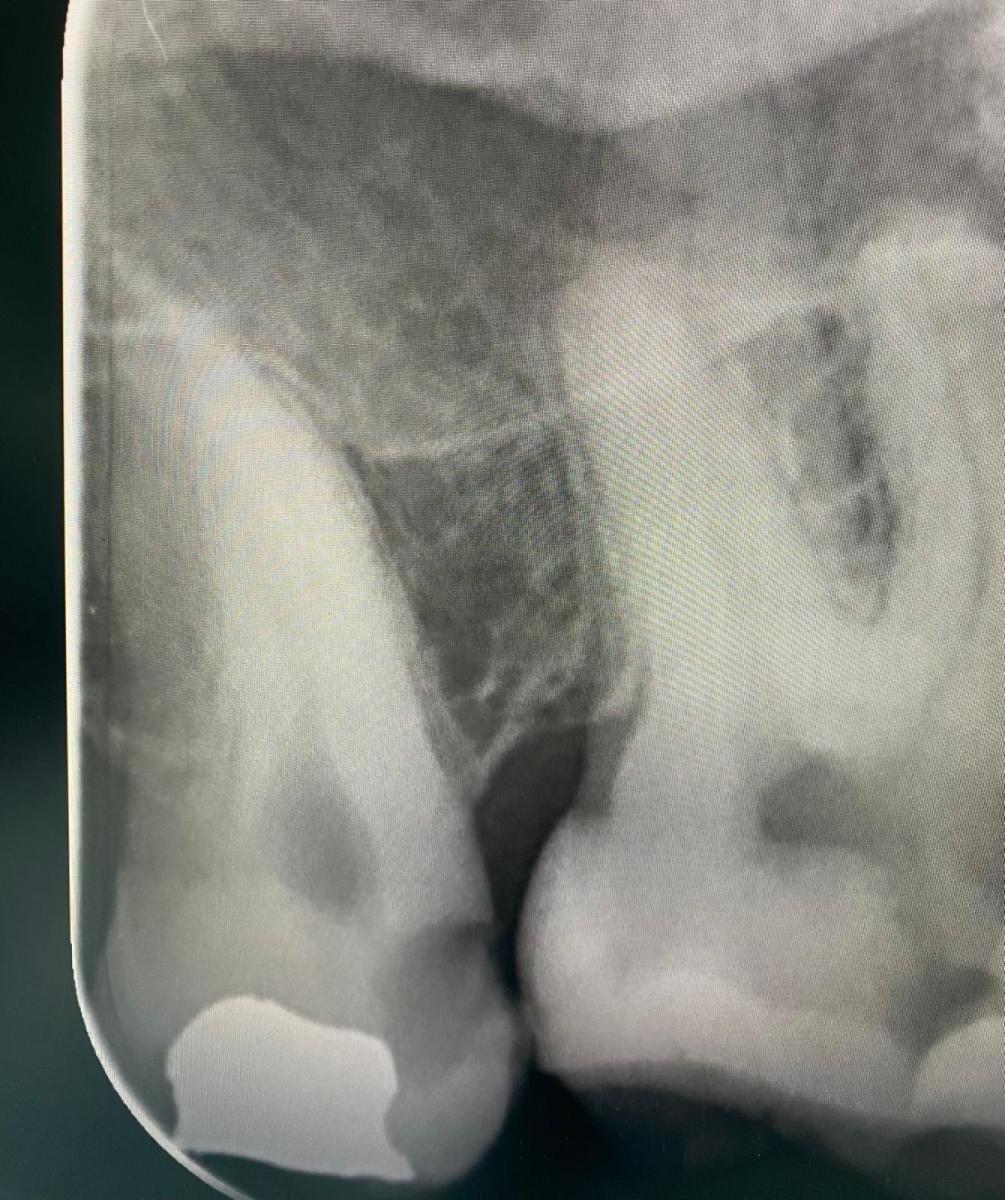

Спасибо Вам. Добовляю снимки до и после.

в 8 на момент снимка оставили временную пломбу. Сказали поменяют через неделю на постоянную. 7 зуб пока не трогали. Сказали 99% каналы чистить.

Скажите пожалуйста правда ли что 8 зубы вобще не нужны даже если не мешают и снизу нет 8? Может всё таки это хорошая опора такой 7?